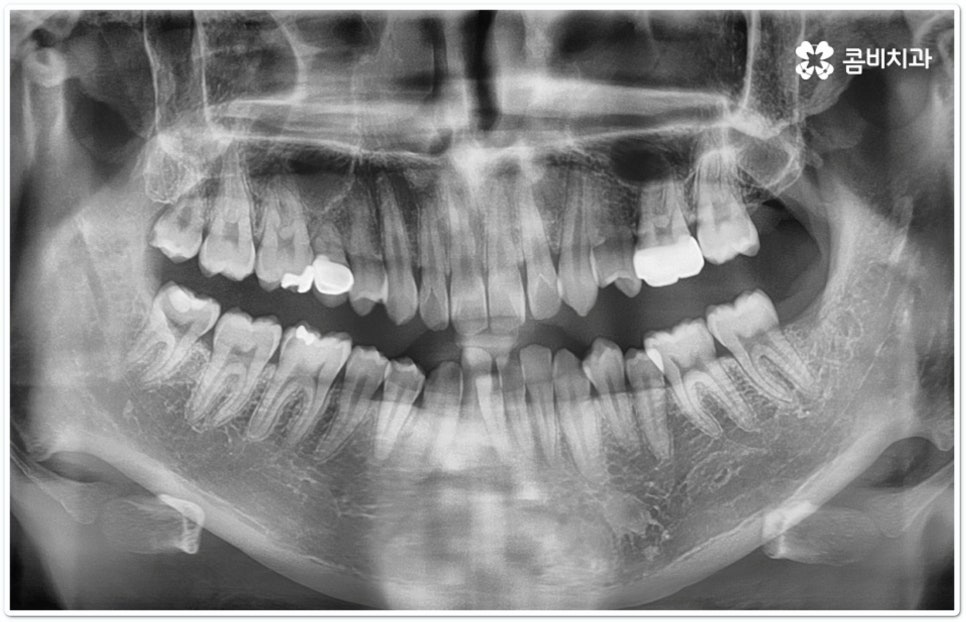

출처 아카이브 열기교정 치료는 교합이 잘 맞지 않거나 치열이 삐뚤어졌을 때 장치를 치아에 부착하여 기능성과 심미성을 회복할 수 있도록 해 주는 것으로 최근들어 관련 기술과 장치 등이 많이 발전하면서 보다 대중화되고 있습니다. 그러면서 예전에 교정을 하고 싶었다가도 오래 걸리고 불편하다, 장치가 겉으로 드러나는 것이 부담스럽다 등등 여러 가지 이유들로 인해 이를 미뤄두셨던 분들 중 다시 치과를 찾아 문의를 주시는 경우가 늘어나고 있는데요.

만약 치열이 많이 삐뚤어지지 않고 부정교합 정도가 심각한 것이 아니라면, 예를 들어 치아 사이가 약간 벌어져 있거나 조금 덧니로 겹쳐진 케이스라면 해당 부위에만 브라켓을 부착하는 부분 교정을 통해 보다 간편하고 신속하게 치열을 고르게 만들 수 있지만 대부분은 골격적인 원인이 함께 작용하기 때문에 꼼꼼하게 검진을 해 본 후 전체 치아 이동을 통해 교합을 맞춰줄 필요가 있다는 진단 결과가 나오는 경우가 더 많이 있는 거예요.

또한 혹시라도 치아 이동을 할 때 통증을 많이 느끼는 것이 교정 치료 기간을 단축시킬 수 있는 방법이 아닐까 궁금해 하실 수 있는데 과도한 통증이라는 것은 무리한 진행을 의미하며 중장년 성인분들의 경우 성장기 환자에 비해 잇몸뼈가 단단하고 교정 치료 중 잇몸뼈가 파괴되면서 주변 세포가 다시 활성화 되는 과정에서 시간이 더 오래 걸리는 만큼 이렇게 무리한 치아 이동을 반복하게 되면 오히려 잇몸이 약해지거나 치아 뿌리가 흡수되는 등의 부작용이 생길 수 있으니 주의하실 필요가 있어요. 교정 중에는 음식물이 장치에 끼어 치아에 문제가 생길 가능성도 높아지므로 잇몸 질환이나 충치 등 기본적인 구강 관리도 놓치지 않고 통합적이고 철저하게 케어해 줄 수 있는 치과에서 교정 치료를 진행하시길 권유드리고 있습니다.